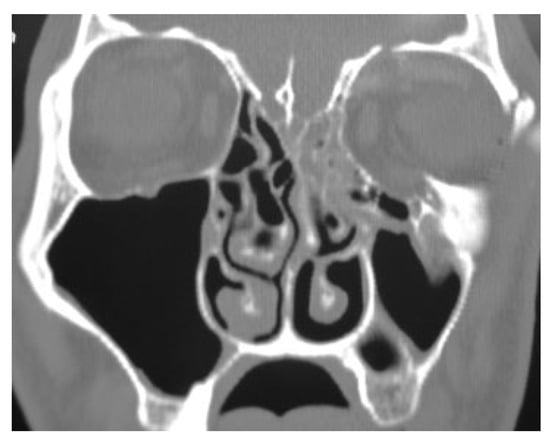

In this prospective study different parameters using biode-gradable plates for reconstruction of the blow-out fractures were assessed. The study was approved by the research committee of the medical ethics group of Shiraz University of Medical Sciences. The study sample was derived from the patients who referred to the Department of Craniomaxillo-facial Surgery for evaluation and management of orbital fracture between January 2009 and December 2010. Patients eligible for study inclusion had an impure blow-out fracture and there was a need to repair orbital floor and to fix the zygomaticomaxillary complex in a proper position. Patients who had pure blow-out fracture or minimal bone displace-ment in computed tomography (CT) scan views without the enophthalmos or the diplopia were excluded from the study. All the patients had a recent trauma and subsequently surgi-cal intervention was made between 1 and 10 days. A consul-tation was made with ophthalmologist before the surgical intervention. An axial and coronal CT scans were taken through 2-mm cuts for each patient before surgical interven-tion, immediate, and 18 months after surgery (Figure 1 and Figure 2). The amount of the orbital floor defect was measured in each case through CT scan. The surgical approach consisted of mid-lower incision for accessing the orbital rim and floor. Bone reduction and reconstruction was made through biode-gradable plate (PG910/PDO) (Figure 3). Titanium miniplates and screws were used for fixation of fractured infraorbital rim. The thickness of the biodegradable plates (PG910/PDO) was 0.5 mm. All the patients underwent secondary interven-tion to remove the titanium miniplates after 18 months. The orbital floor was reevaluated during the secondary interven-tion. The evaluation of remnant defects and biodegradable plates (complete or partial resorption) was made for every patient (Figure 4).

Figure 2. A coronal view shows a remnant defect 18 months after reconstruction.